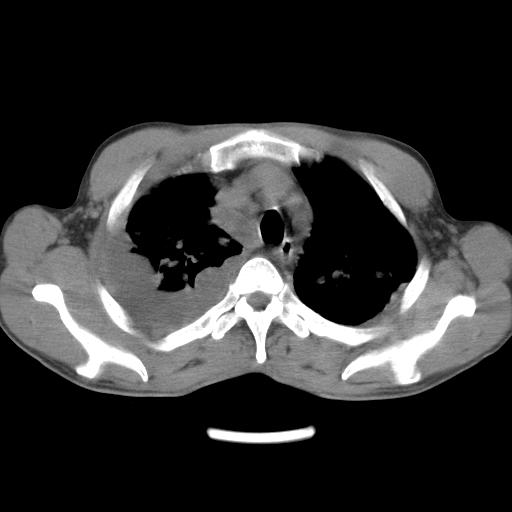

男性,44岁,结核病史多年。现胸闷气短,咳嗽,偶咳血。

右侧胸腔积液

右肺下叶不张

双肺多发结节影最分空洞形成考虑占位不除外结核

双肺陈旧性病变

1、右侧大量胸腔积液伴右肺压缩性膨胀不全,建议抽液治疗后复查 2、两肺继发性tb伴空洞形成。

1)两肺继发性肺结核伴空洞形成,左肺多发性结核球。2)右侧大量胸腔积液伴右肺部分膨胀不全。3)纵隔淋巴结肿大。